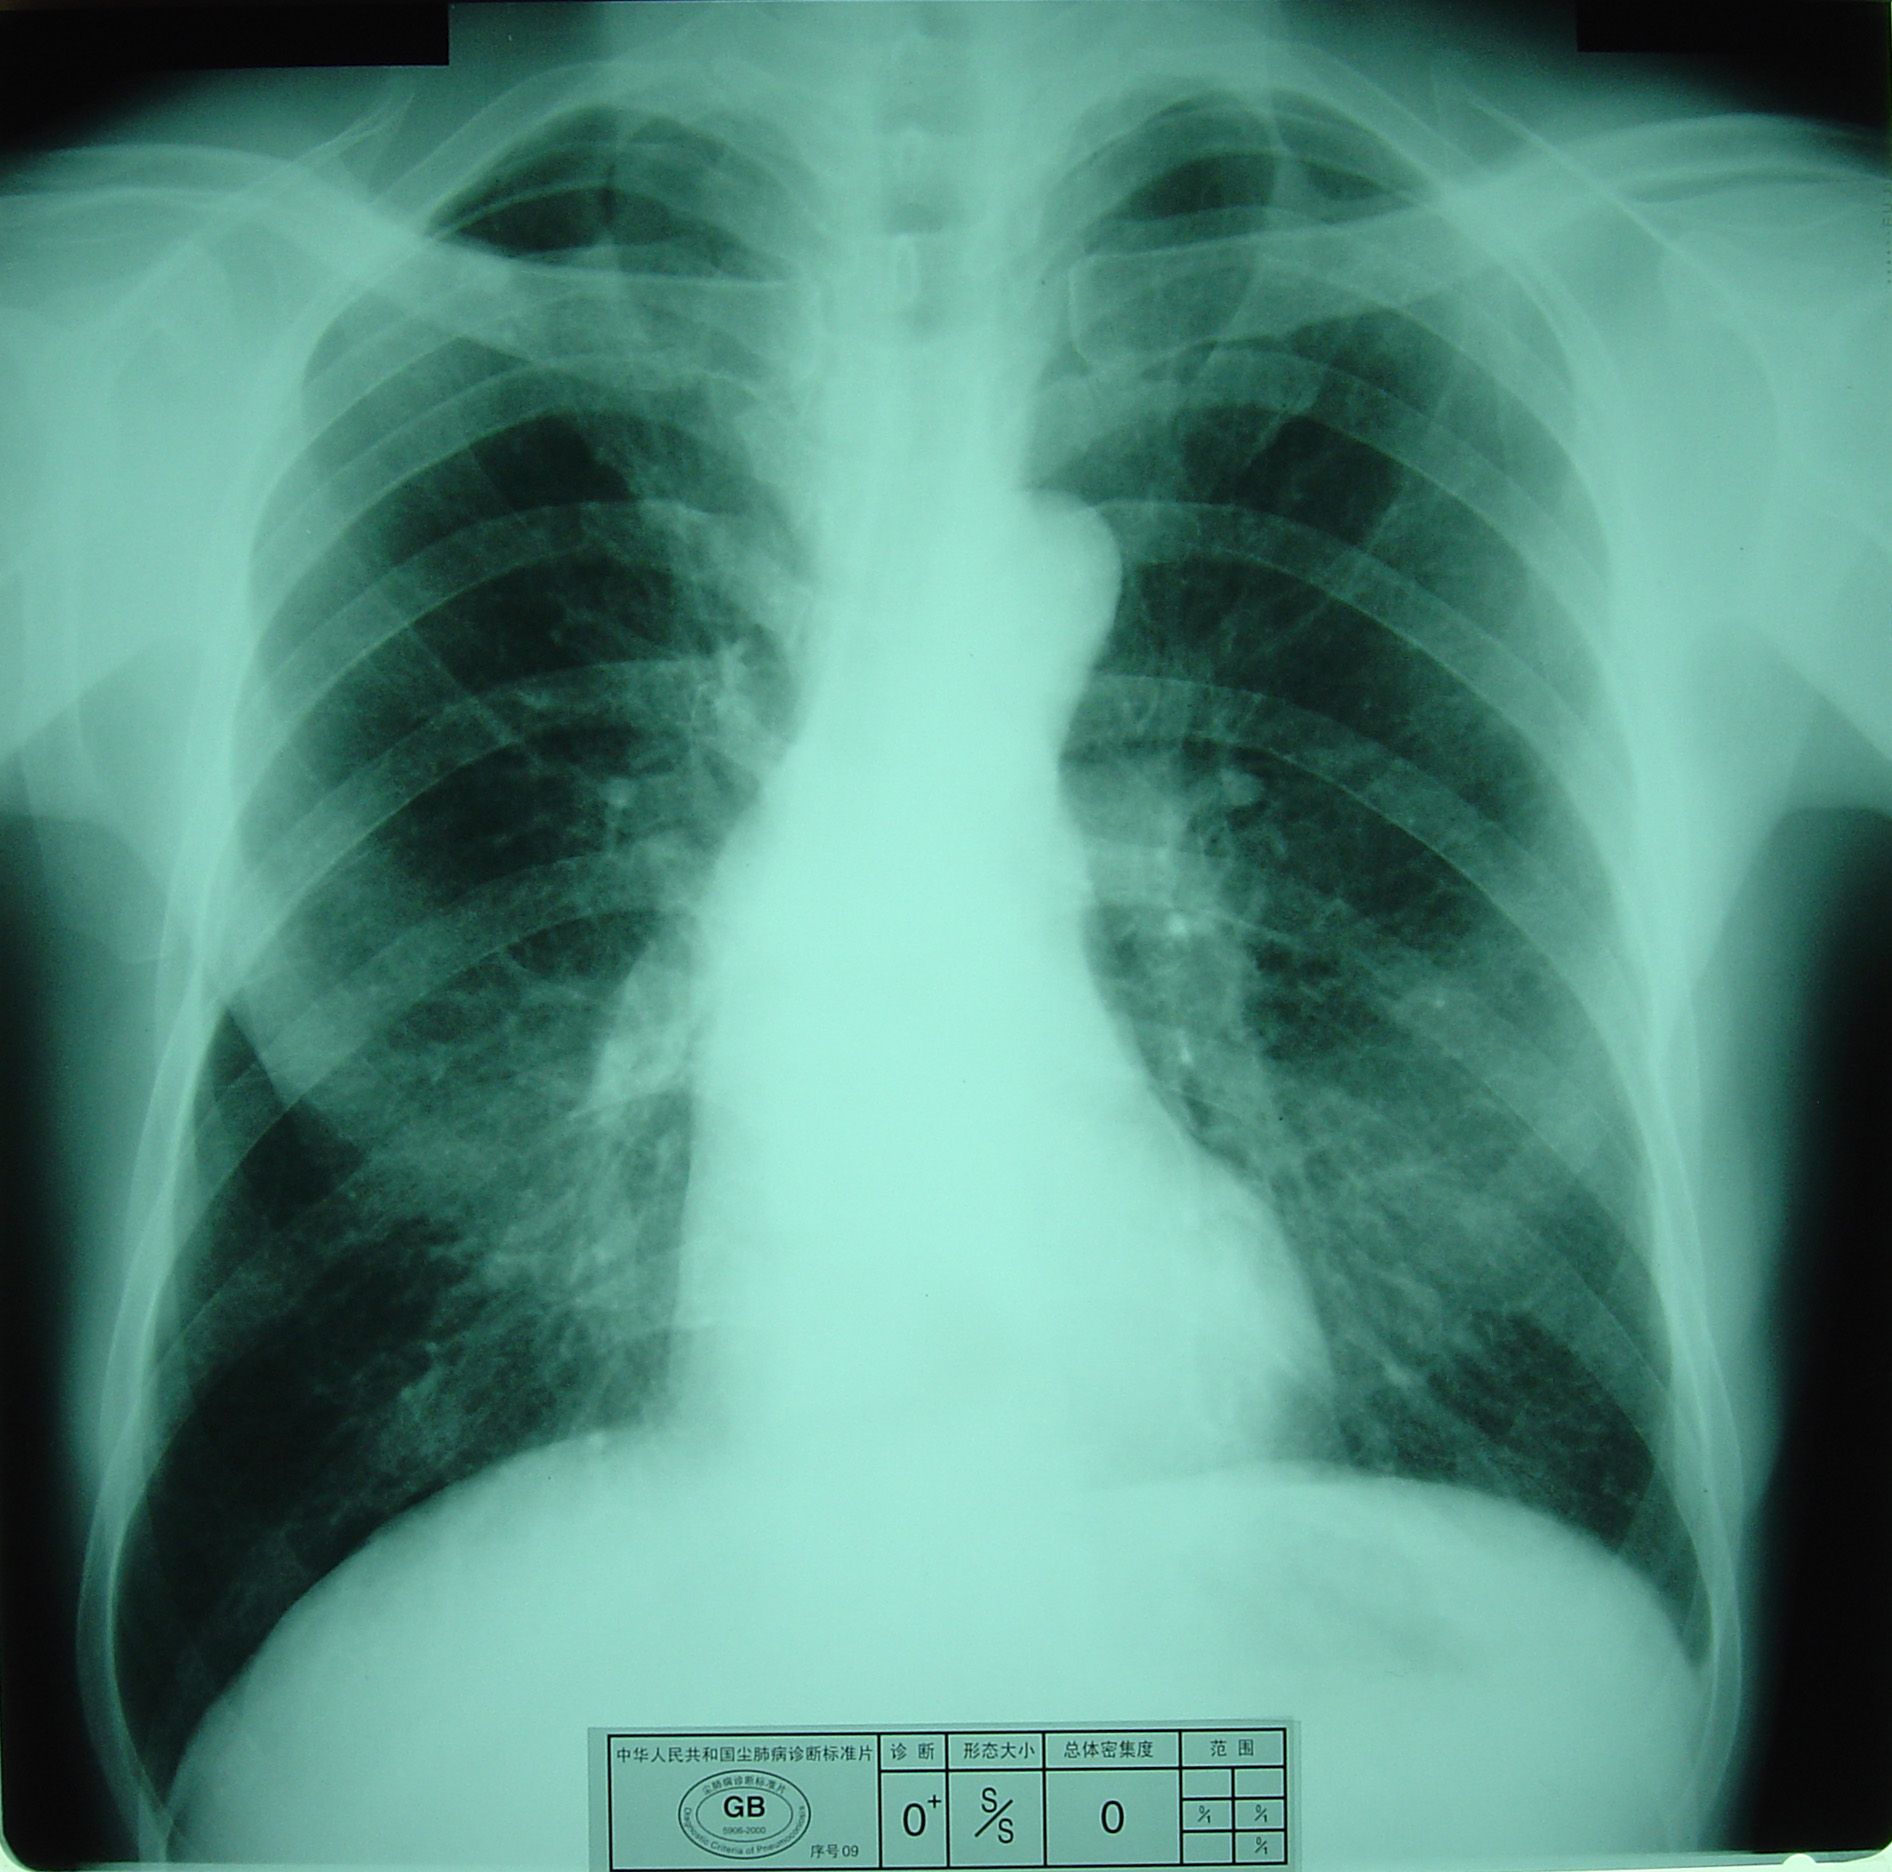

(2)X射线胸片表现:矽肺X射线胸片影像是肺组织矽肺病理形态在X射线胸片的反映,是“形”和“影”的关系,与肺内粉尘蓄积、肺组织纤维化的病变程度有一定相关关系,但由于多种原因的影响,并非完全一致。这种X射线胸片改变表现为X射线通过病变组织和正常组织对X射线吸收率的变化,呈现发“白”的圆形或不规则形小阴影,作为矽肺诊断依据。X射线胸片上其他影像,如肺门变化、肺气肿、肺纹理和胸膜变化,对矽肺诊断也有参考价值。在X射线胸片上,肺野内直径或宽度不超过10mm的阴影。小阴影按其形成分为圆形和不规则形两类。

2)不规则形小阴影:多为接触游离二氧化硅含量较低的粉尘所致,病理基础主要是肺间质纤维化。表现为粗细、长短、形态不一的致密阴影。阴影之间可互不相连,或杂乱无章的交织在一起,呈网状或蜂窝状;致密度多持久不变或缓慢增高。按其宽度可分为s(<1.5mm)、t(1.5~3.0mm)、u(3.0~10mm)三种类型。早期也多见于两肺中下区,弥漫分布,随病情进展而逐渐波及肺上区。

不规则形小阴影(s类小阴影)

尘肺壹期:有下列表现之一者:

a)有总体密集度1级的小阴影,分布范围至少达到2个肺区。

观察对象

无尘肺